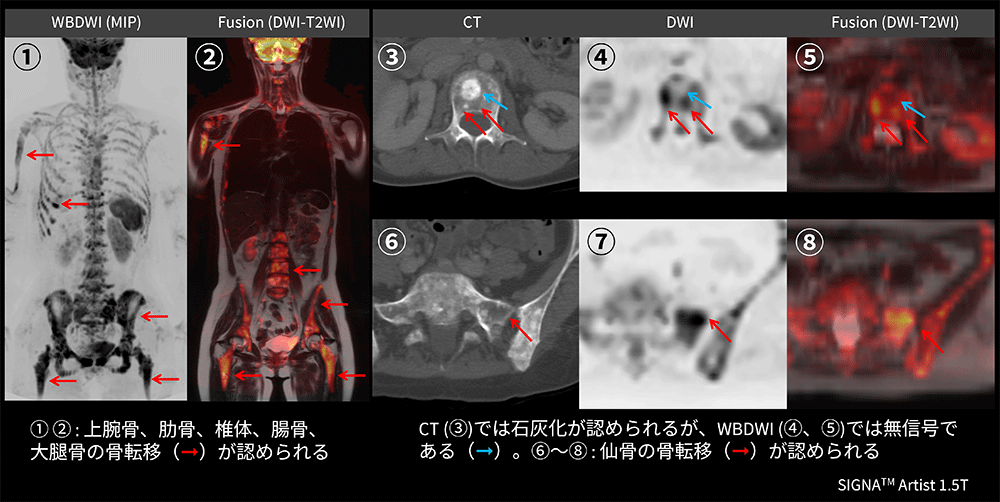

Case2 乳腺外科:乳癌の全身検索目的

40代、女性。乳癌術後にて5年前に肝転移に対して治療開始。その後、CTにて骨転移とリンパ節転移を認め、全身検索目的にてWBDWIを施行した。WBDWI(①)とFusion(②)で上腕骨、肋骨、椎体、大腿骨など多発骨転移が認められる。CT(③)では椎体の中心に石灰化(➞)を認めるが、DWI(④)とFusion(⑤)では無信号であることから良性石灰化を疑う所見である。CT(③)の石灰化周囲(➞)にDWI(⑦)で高信号を認め、溶骨性骨転移を示唆する所見である。また、仙骨にも同様のCT(⑥)の低吸収域(➞)にDWI(⑦)でも同部位に高信号を認め、溶骨性骨転移が疑われる(図11)。依頼医からは、乳癌のフォローは長期にわたり定期的に画像検査を行う必要があるため、WBDWIは被ばくがなく、繰り返し検査を行うことが可能であるため非常に有用であると評価が得られた。

Architect_Okazakishimin02_14.png

図11 乳癌術後の全身検索目的